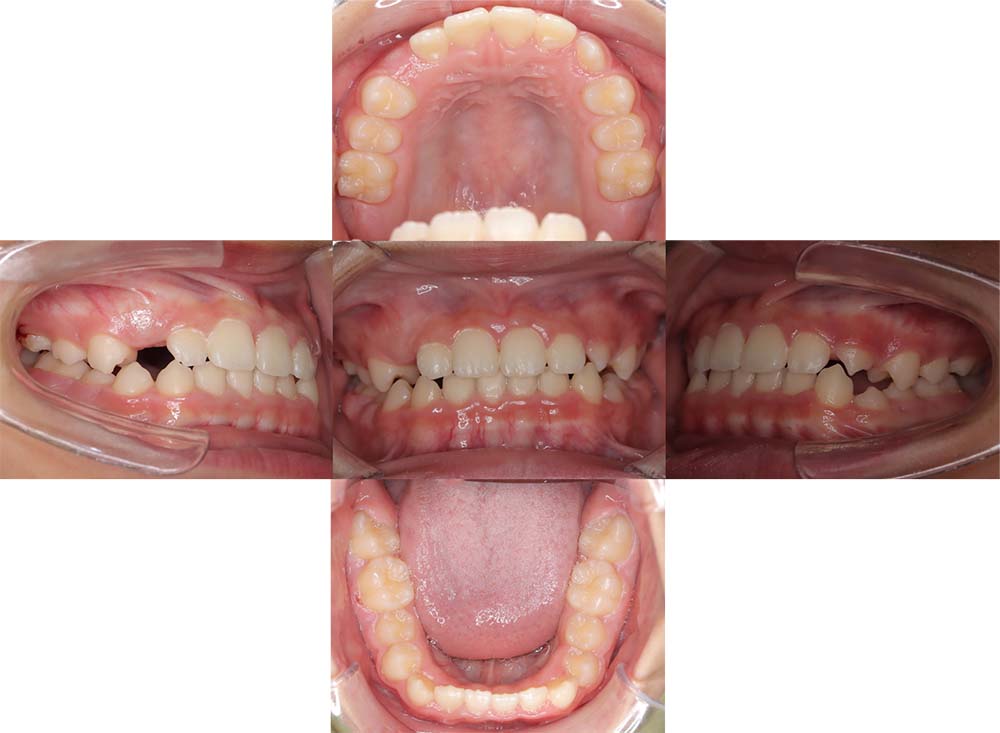

症例01

| 主訴 | 歯並びがガタガタしている。 |

| 診断名あるいは主な症状 | 叢生 |

| 年齢/性別 | 22歳・男性 |

| 矯正ステージ | 大人の矯正治療 |

| 治療方法 | ワイヤー矯正 |

| 抜歯部位/抜歯有無 | 非抜歯 |

| 治療内容 | 上顎大臼歯の遠心移動により前歯のガタガタを排列スペースを獲得し全顎的な排列を行った。 |

| 費用 | 85万円程度(2025.10時点の料金となります。) ※矯正基本料金、審美ブラケットを含む |

| 治療期間 | 2年4ヶ月 |

| 主なリスク・副作用 | 痛み、歯根吸収、歯肉退縮、虫歯、後戻り |